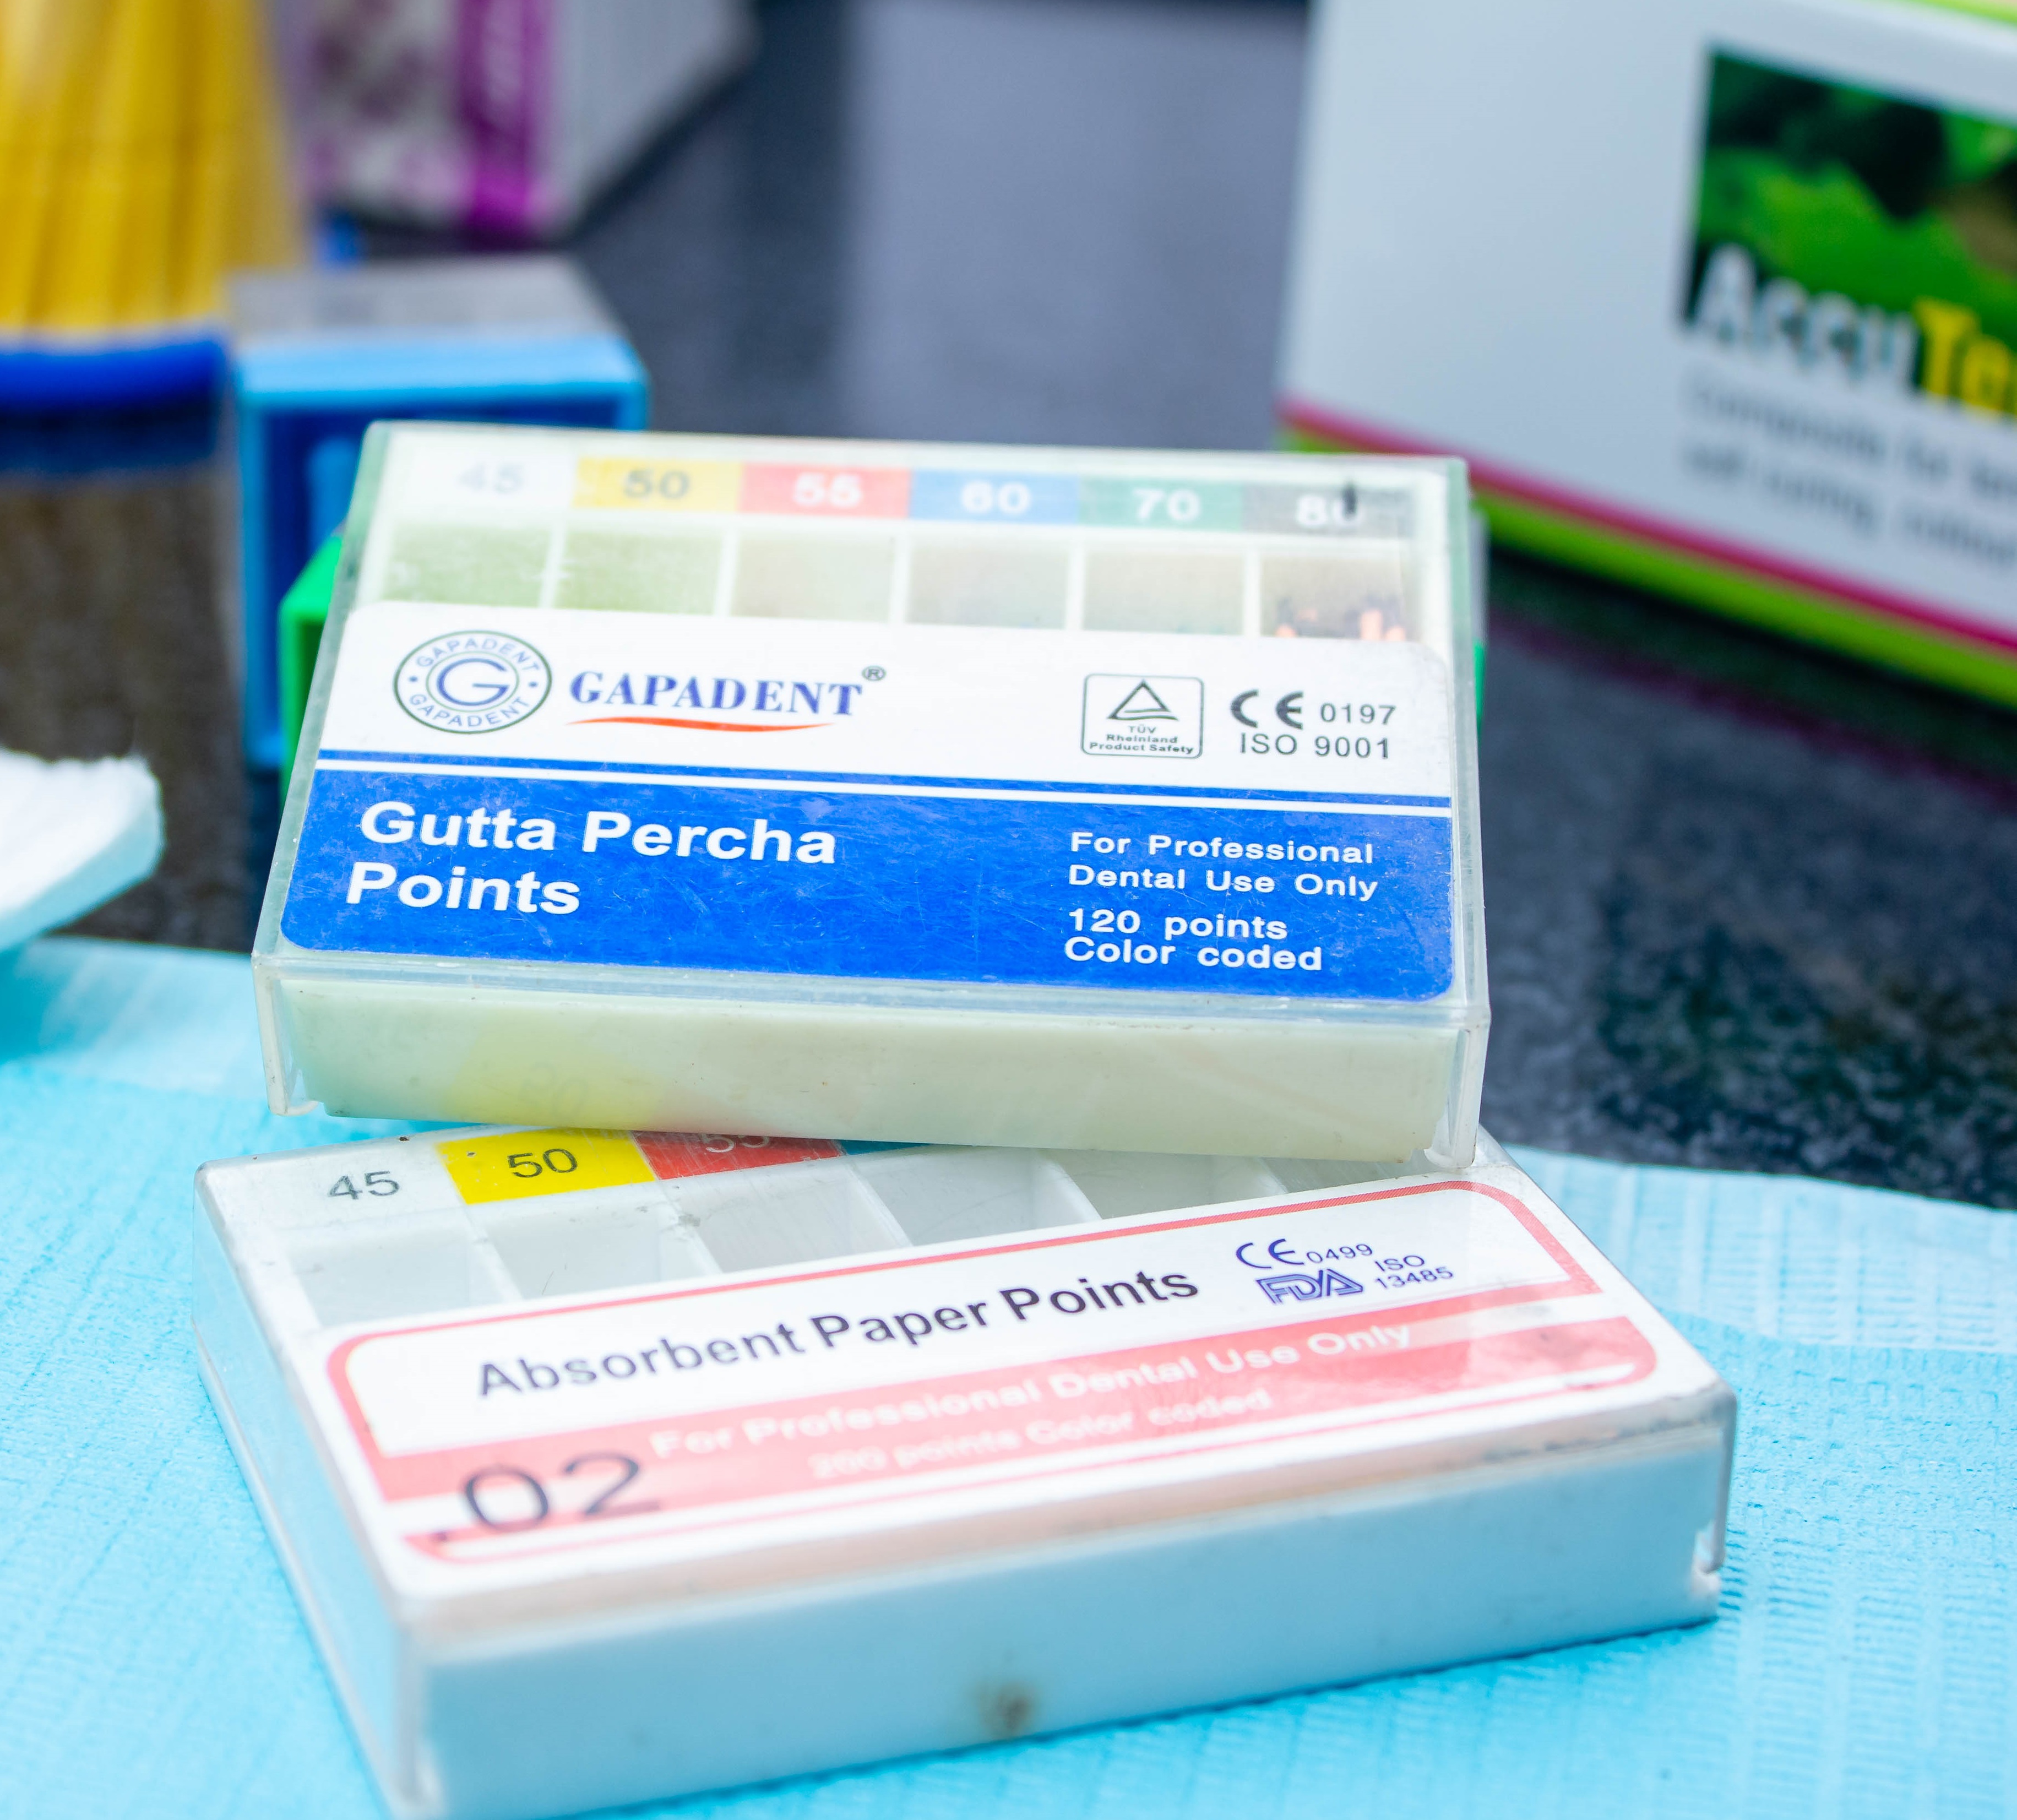

We offer a wide range of services to help you achieve and maintain a healthy and beautiful smile. Our team of experienced and skilled dental professionals is committed to providing you with the highest quality of care in a comfortable and welcoming environment.

Why Choose 4th Street Dental Clinic? Exceptional dental care in a comfortable and welcoming environment, Experienced and compassionate dental professionals, Personalized care for each patient, Commitment to preventative care and education, Use of the latest technology and techniques and Affordable dental care for everyone